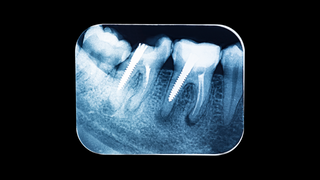

Panoramic x-rays

Tooth x-rays